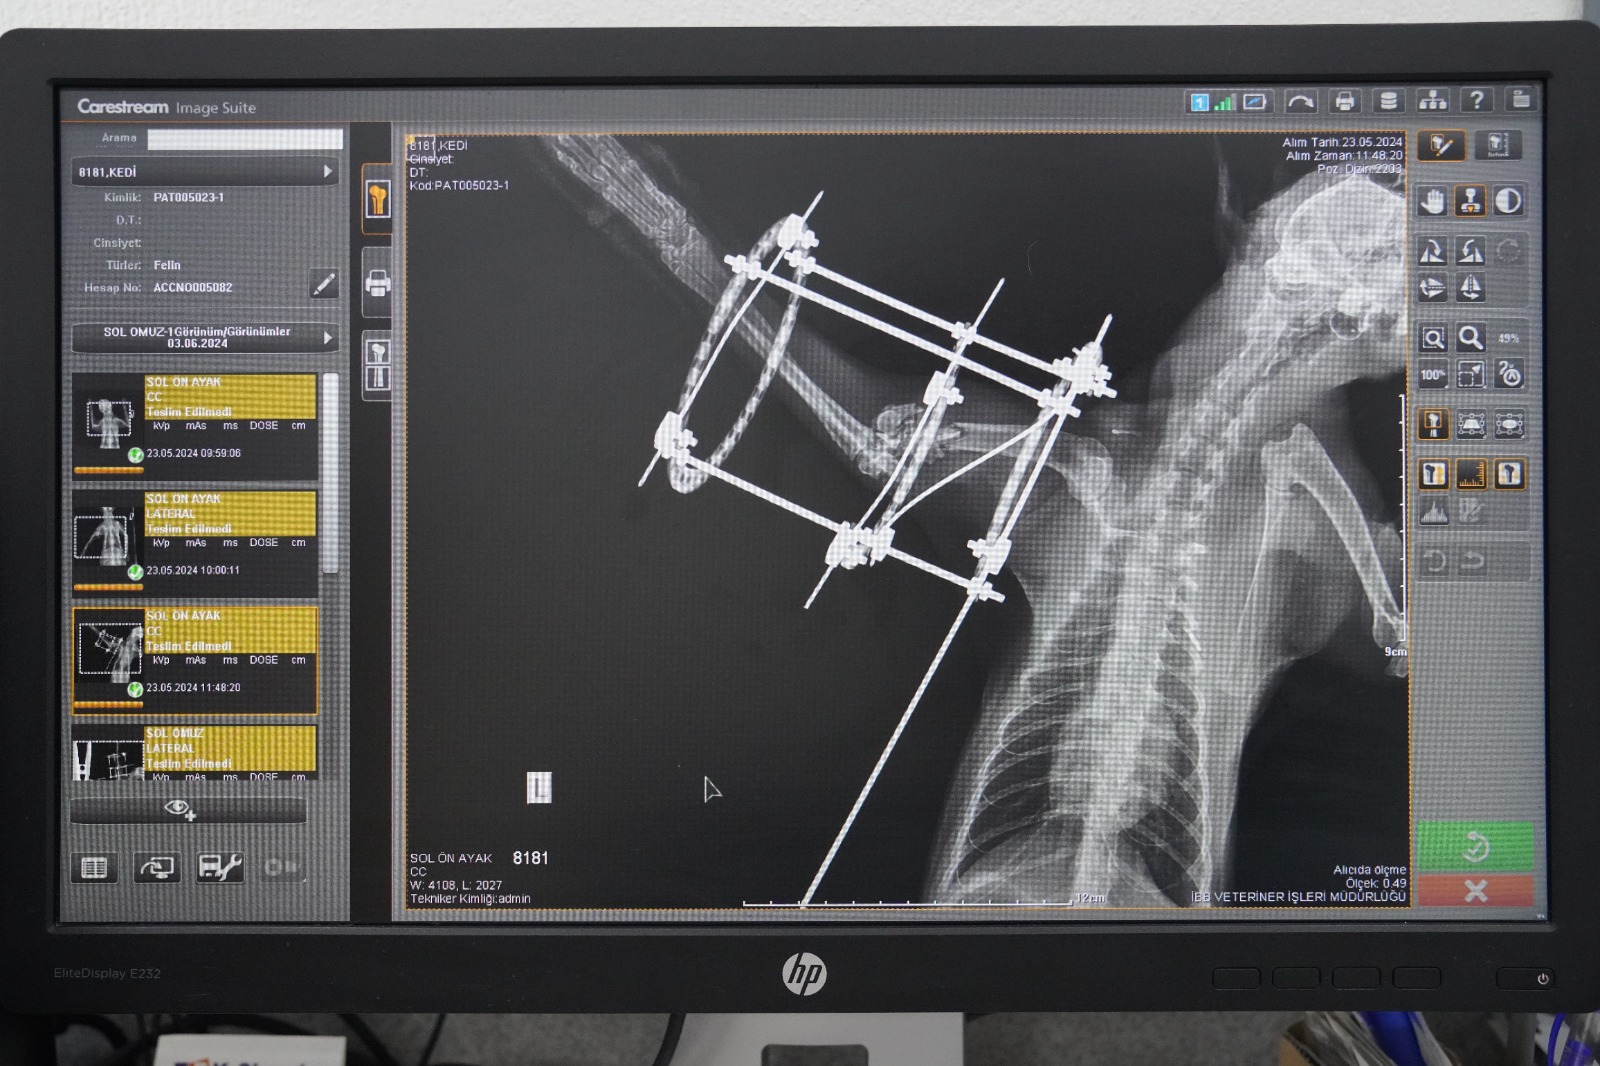

Ameliyat hakkında bilgi veren Veteriner Hekim Mehmet Uysal, ortopedi biriminde kedinin bacağının durumunu tespit ettiklerini belirterek, “Bacağının ciddi şekilde parçalandığını gördük. Burada sağlığına kavuşması için hemen gerekli cerrahi tedaviyi uyguladık. Bacağında parçalanan kemikleri özel bir aparatla sabitledik. Güvenli bir yöntem olduğu için bunu tercih ettik. Kedimiz 25 gündür bu şekilde tedavi altında. Bir süre sonra bu taktığımız aparatın kırıklar üzerindeki etkisine bakacağız. Bacak iyileşmiş olursa çıkaracağız. Şu anda sağlığı ile alakalı bir problemi yok. Keyfi yerinde. Bacağını nasıl kullanacağını öğreniyor diyebilirim” diye konuştu.